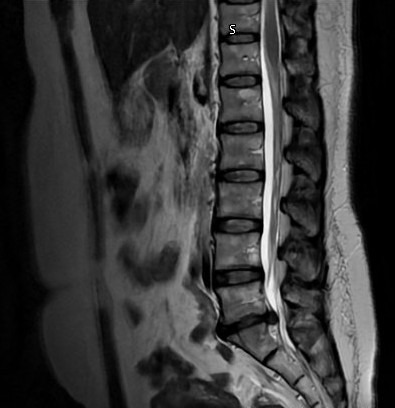

Con el corazón lleno de esperanza, acudo a ustedes solicitando apoyo financiero para una urgencia médica. He sido diagnosticada con una hernia discal extruida en L5-S1 la cual está ejerciendo presión en ambos lados de la médula espinal causando dolor lumbar que irradia hacia mis piernas. Esto ha tenido un gran impacto en mi movilidad. Por lo que requiero una cirugía urgente para descompresión y extracción de la hernia.

El IMSS me ofrece una cirugía abierta muy invasiva, con colocación de tornillos y varillas, además de que el tiempo aproximado para que pueda recibir la cirugía en el seguro es aproximadamente de 6 meses. Tiempo que definitivamente no puedo esperar.